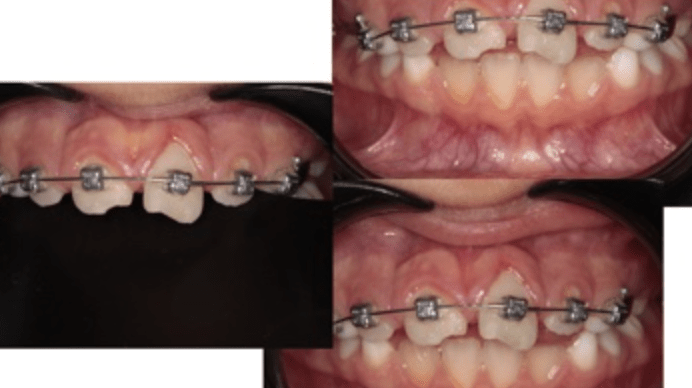

Pulpotomías

Gingivectomía + pulpotomía biodentine + reconstrucción

Pulpotomía biodentine + reco preendio

Pulpotomía diente temporal